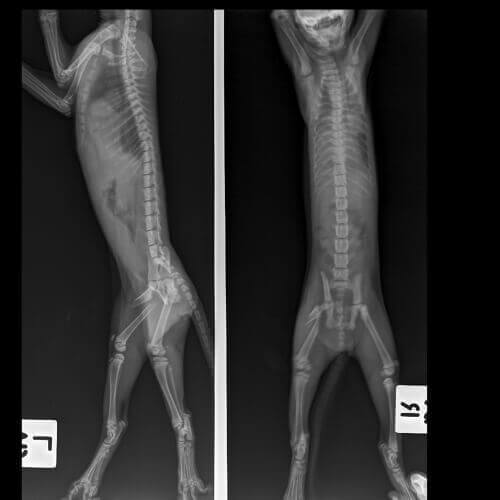

Kedilerde sakatlık: Teşhis

Eğer kediniz düzgün bir şekilde muayene olursa ve rahatsızlığı doğru bir şekilde teşhis edilirse, kalıcı bir kas veya sinir problemine sahip olmadan bu süreci atlatabilmeniz mümkündür. Veterineriniz kedinizin sorununun kökenine inebilmek için kapsamlı testler uygulayacaktır.

Kedinizin yaşı, sakatlık geçmişi, mevcut problemin akut veya kronik olması, sakatlık seviyesinin ciddiyeti veya kaç bacağında sorun olduğu, doğru teşhiste bulunulması açısından göz önüne alınması gereken faktörlerdir.

Kedinizin yaşadığı sorununun teşhis edilmesi için aşağıdaki testlerden bir veya birkaçı gerekebilir:

- X-ray

- Biyopsi

- Enfeksiyonu ve bağışıklık sistemini kontrol etmek için çeşitli kan testleri

- Ultrason, CT (Bilgisayarlı tomografi), manyetik rezonans görüntüleme